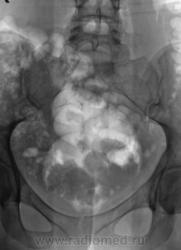

Из анамнеза известно, что примерно 2 месяца тому "летела" со сноутборга около 200 метров. Сейчас беспокоят боли в области спины, крестца и лонного сочленения. УЗИ было сделано всего, что только можно, везде - "норма". Хирурги, вроде-бы тоже ничего не находят. Но боли, видать значительные, походка вынужденная. На рентгенографию была направлена, как жест отчаяния, мол может быть, что-то найдут.

Рентгенограмма в прямой проекции.

1. Не исключаю поперечный перелом S5.

2. Лонное сочленение очевидно,подверглось значительному растяжению (имеется локальный вакуум-феномен слева), умеренно выраженые явления симфизита (опять же - постравматического).

Посттравматический симфизит - это такой медицинский диагноз есть? Тогда уж лучше - симфизопатияУлыбаюсь.  По поперечному перелому Л5 - тангенциальный эффект, сложение теней. По хорошему, надо бы доснять поясничный отдел позвоночника, в том числе в косых проекциях - на дугоотростчатые суставы, и грудо-поясничный переход.

- единственное что ещё увидел - п/травматический остеохондроз/остеоартроз Cs 2-Cs 3 (а, может, и до травмы так было?.. -

Поздно заметил ветку.. увидел симфизит, перелом остистого L4, мазоль Co 5, и  конечно spina bifida S1 ))) глянуть бы межпозвоночные..